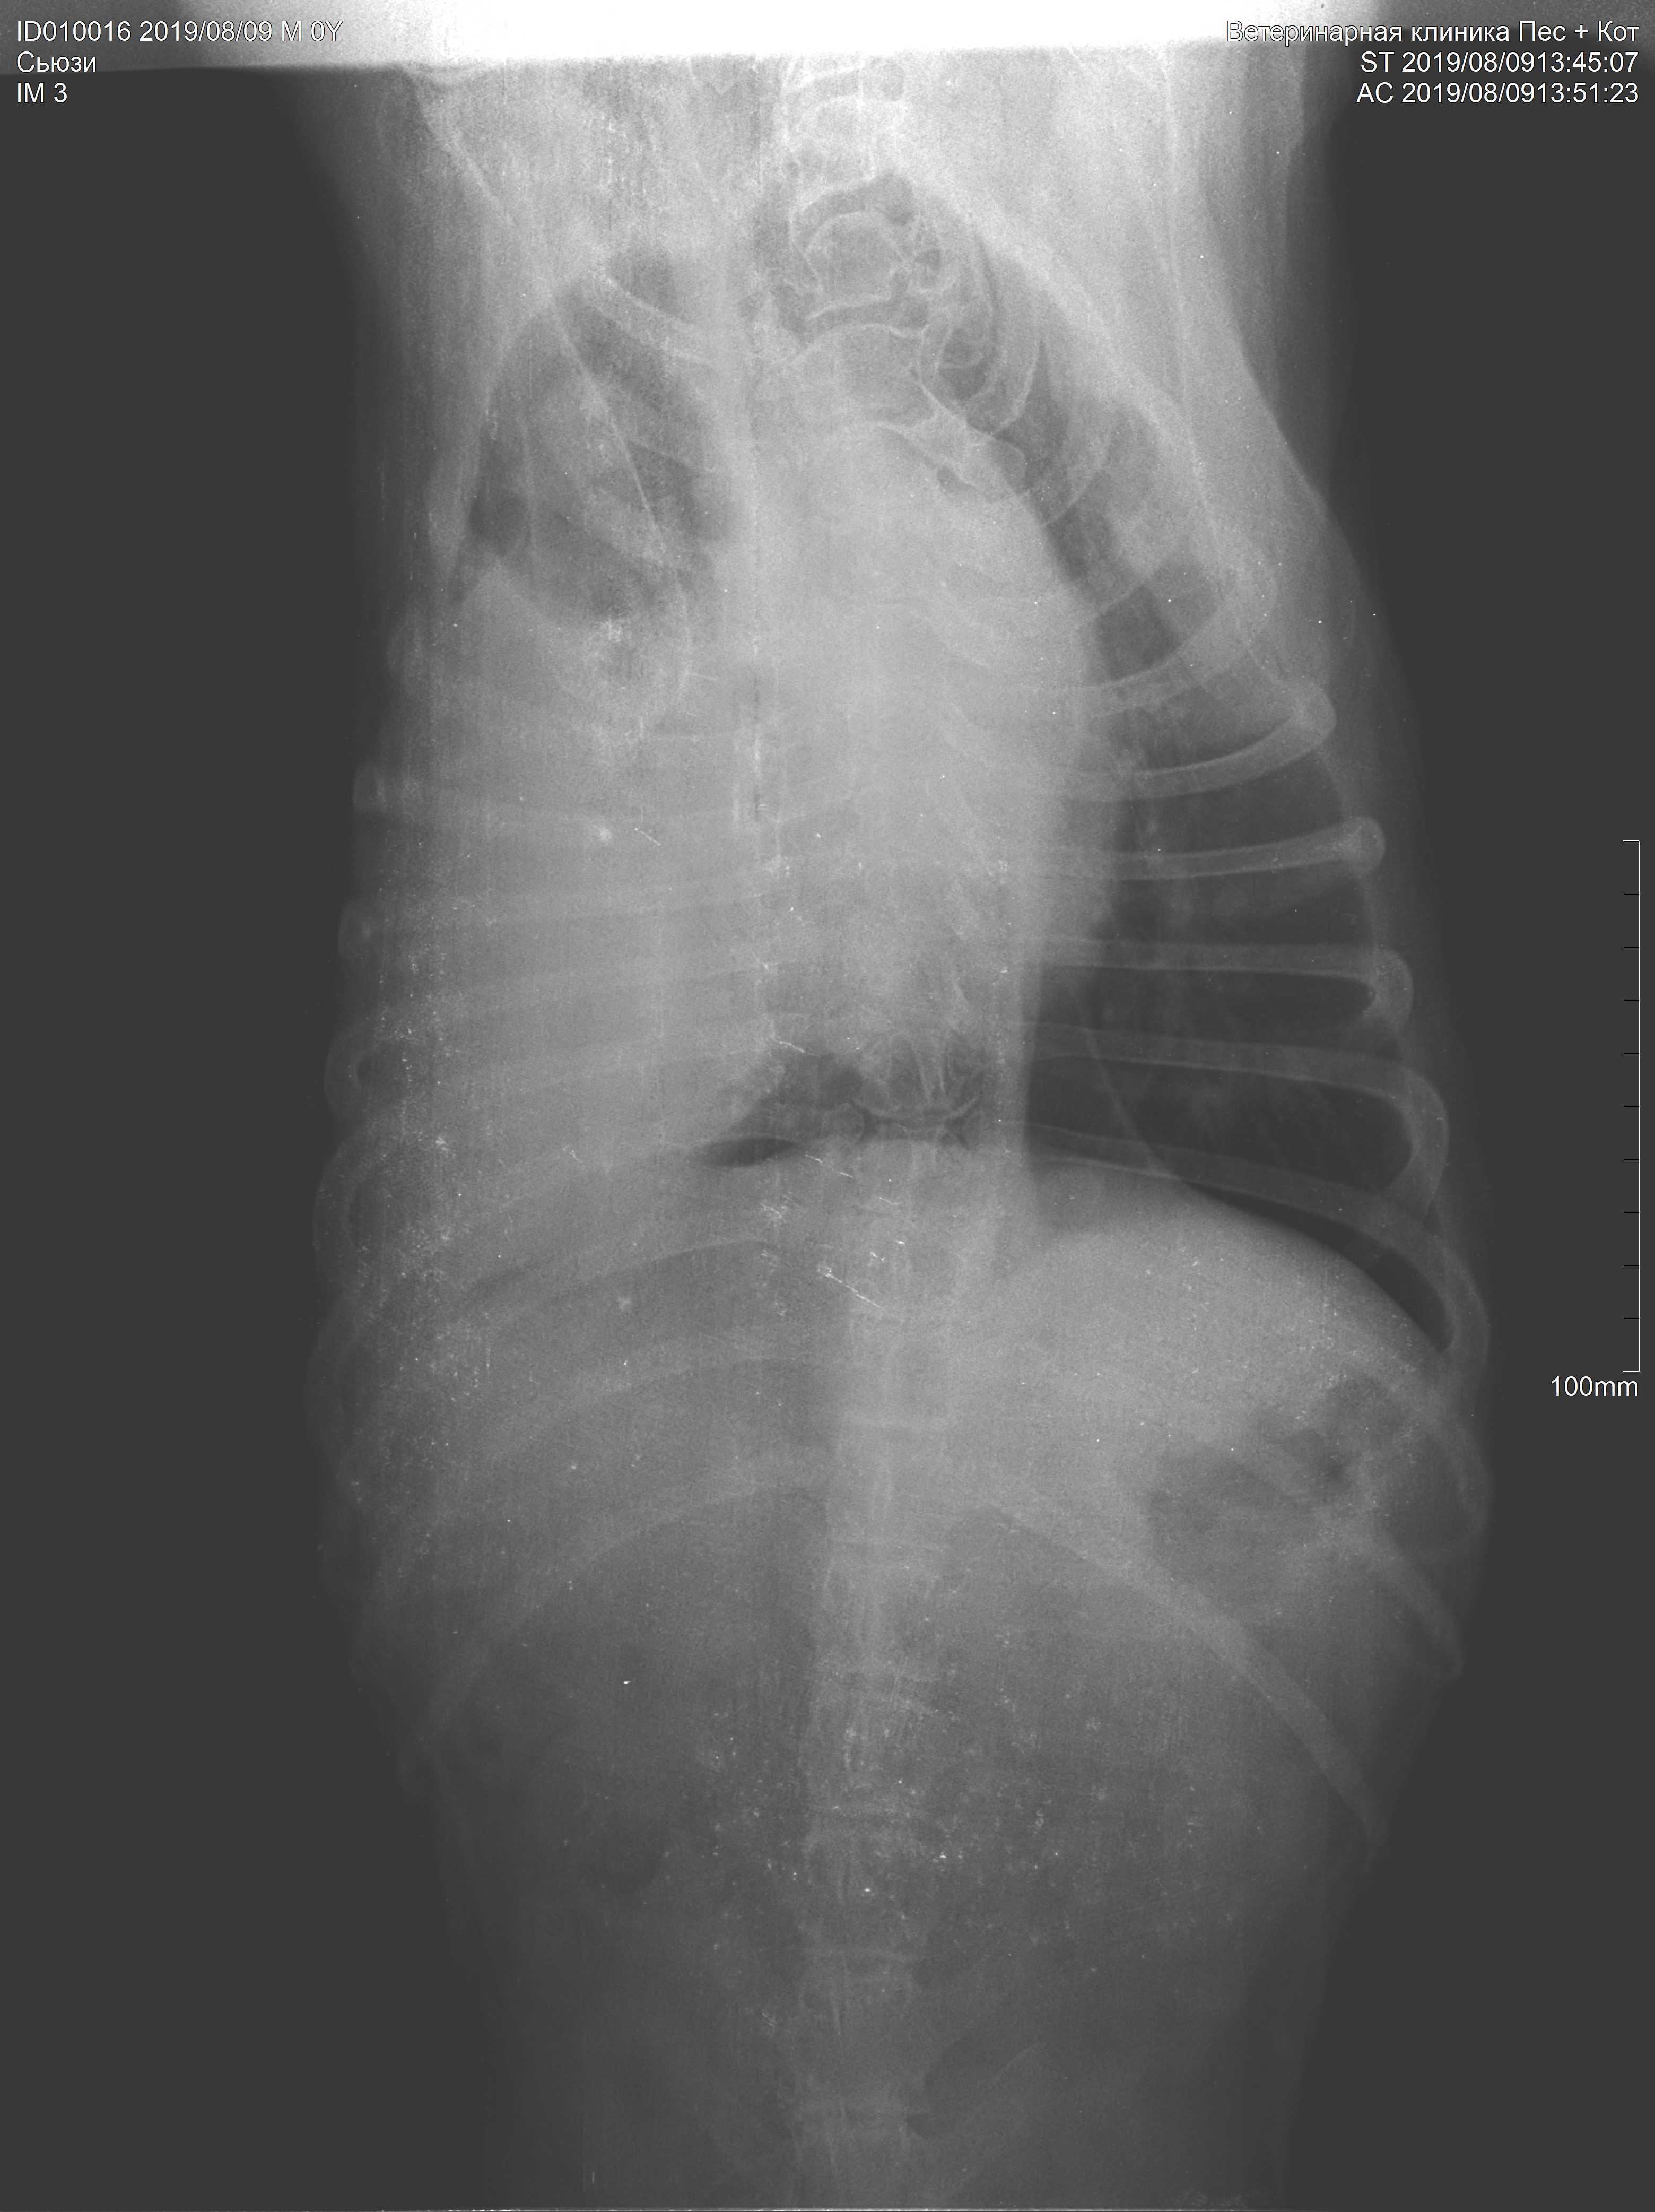

Pet's info: Dog | Boxer | Female | spayed | 10 years and 9 months old | 35 lbs

What's on the Х-ray? Please help me understand. 10-year boxer dog, severe non-productive cough, loosing weight, weakening. Good appetite, good looking hair.

Hello. Unfortunately it looks like Suzy has a tumor or some other very large space occupying mass involving almost 75% of her thoracic cavity. Suzy would need further diagnostics, such as a biopsy, to identify exactly what is in her lungs, but the condition looks very advanced. I hope your veterinarian is making her as comfortable as possible. Thanks for using Petco Pet Education Center, formerly Petcoach.